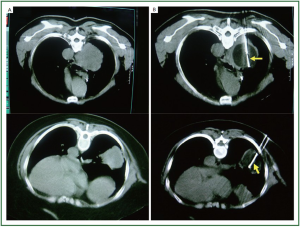

Under the CT guidance, the cryoprobe is inserted into the targeted tumor directly. The cryoprobe uses high-pressure argon and helium gas for freezing and thawing, respectively, on the basis of the Joule-Thompson principle. Cryoablation consists of 2 cycles of 5 minutes of freezing (cooled to around –165 ˚C) followed by slow thawing up to 20 °C and then a third cycle of 10 minutes of freezing followed by thawing. The air in the lung can interfere with the creation of iceball. When the cryoprobe is inserted into normal pulmonary parenchyma, initial freezing can make an iceball of 1 cm in diameter only because the air prevents conduction of low temperatures and there is not enough water in the parenchyma. However, after thawing, the massive intra-alveolar hemorrhage excludes the air and results in a larger iceball that forms in the following freezing. Therefore, three freeze-thaw cycles need to be performed to make an iceball of 2.5 to 3.0 cm in diameter. The 2- or 3-mm diameter cryoprobe can freeze an area of 2 cm and 3 cm in diameter, respectively, and 4 cm long after 3 cycles of freezing and thawing. Therefore, for tumors smaller than 2 cm, only 1 cryoprobe is usually inserted, and for tumors of 2 cm and more in size, 2 or more cryoprobes are used simultaneously to ensure a freezing margin. For those with metastases in both lungs, cryotherapy should be performed separately in an interval of 7 days with each one side for the safety (Figure 1) (15).

Figure 1. Cryotherapy was performed for lung cancer under CT guidance. A. Lung cancer prior to cryoablation; B. Cryoprobe (arrow) surrounded by “ice-ball” (hypodense) during cryoablation.

After procedure, the probe is gently withdrawn. Intraoperative thoracentesis will be performed if pneumothorax or haemopneumothorax is evident by CT scans. Antibiotics and haemostatics if necessary should be administered for 3 days after cryotherapy. While in the old days, after the cryoprobe is removed, fibrin glue is infused into the outer sheath, the outer sheath is removed while the inner sheath is used to push the coagulated fibrin into the cryoprobe track to reduce the risk of bleeding and pneumothorax (15,17).